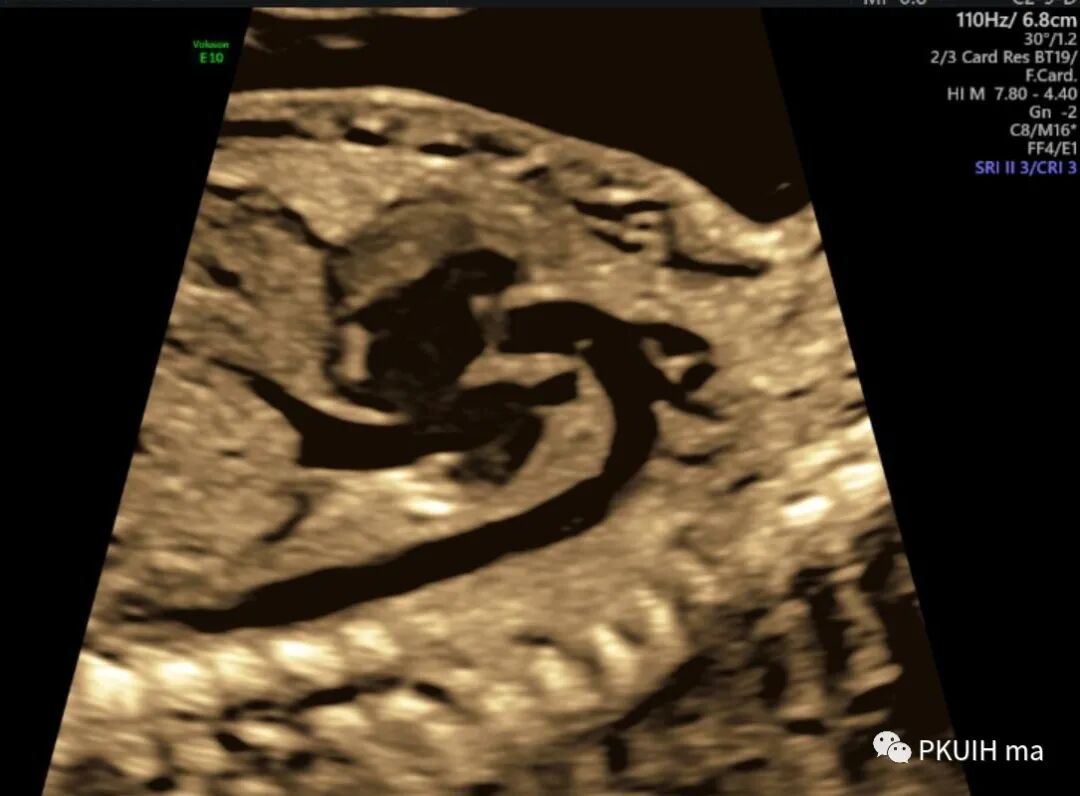

另外,主动脉弓长轴切面显示峡部与降主动脉连接处形态异常,主动脉弓缩窄处与粗大的降主动脉相连,局部形成环形缩窄或后壁向管腔内形成“嵴”样隆起,故称之为“缩窄环”,又称 “支架征” 。如下图